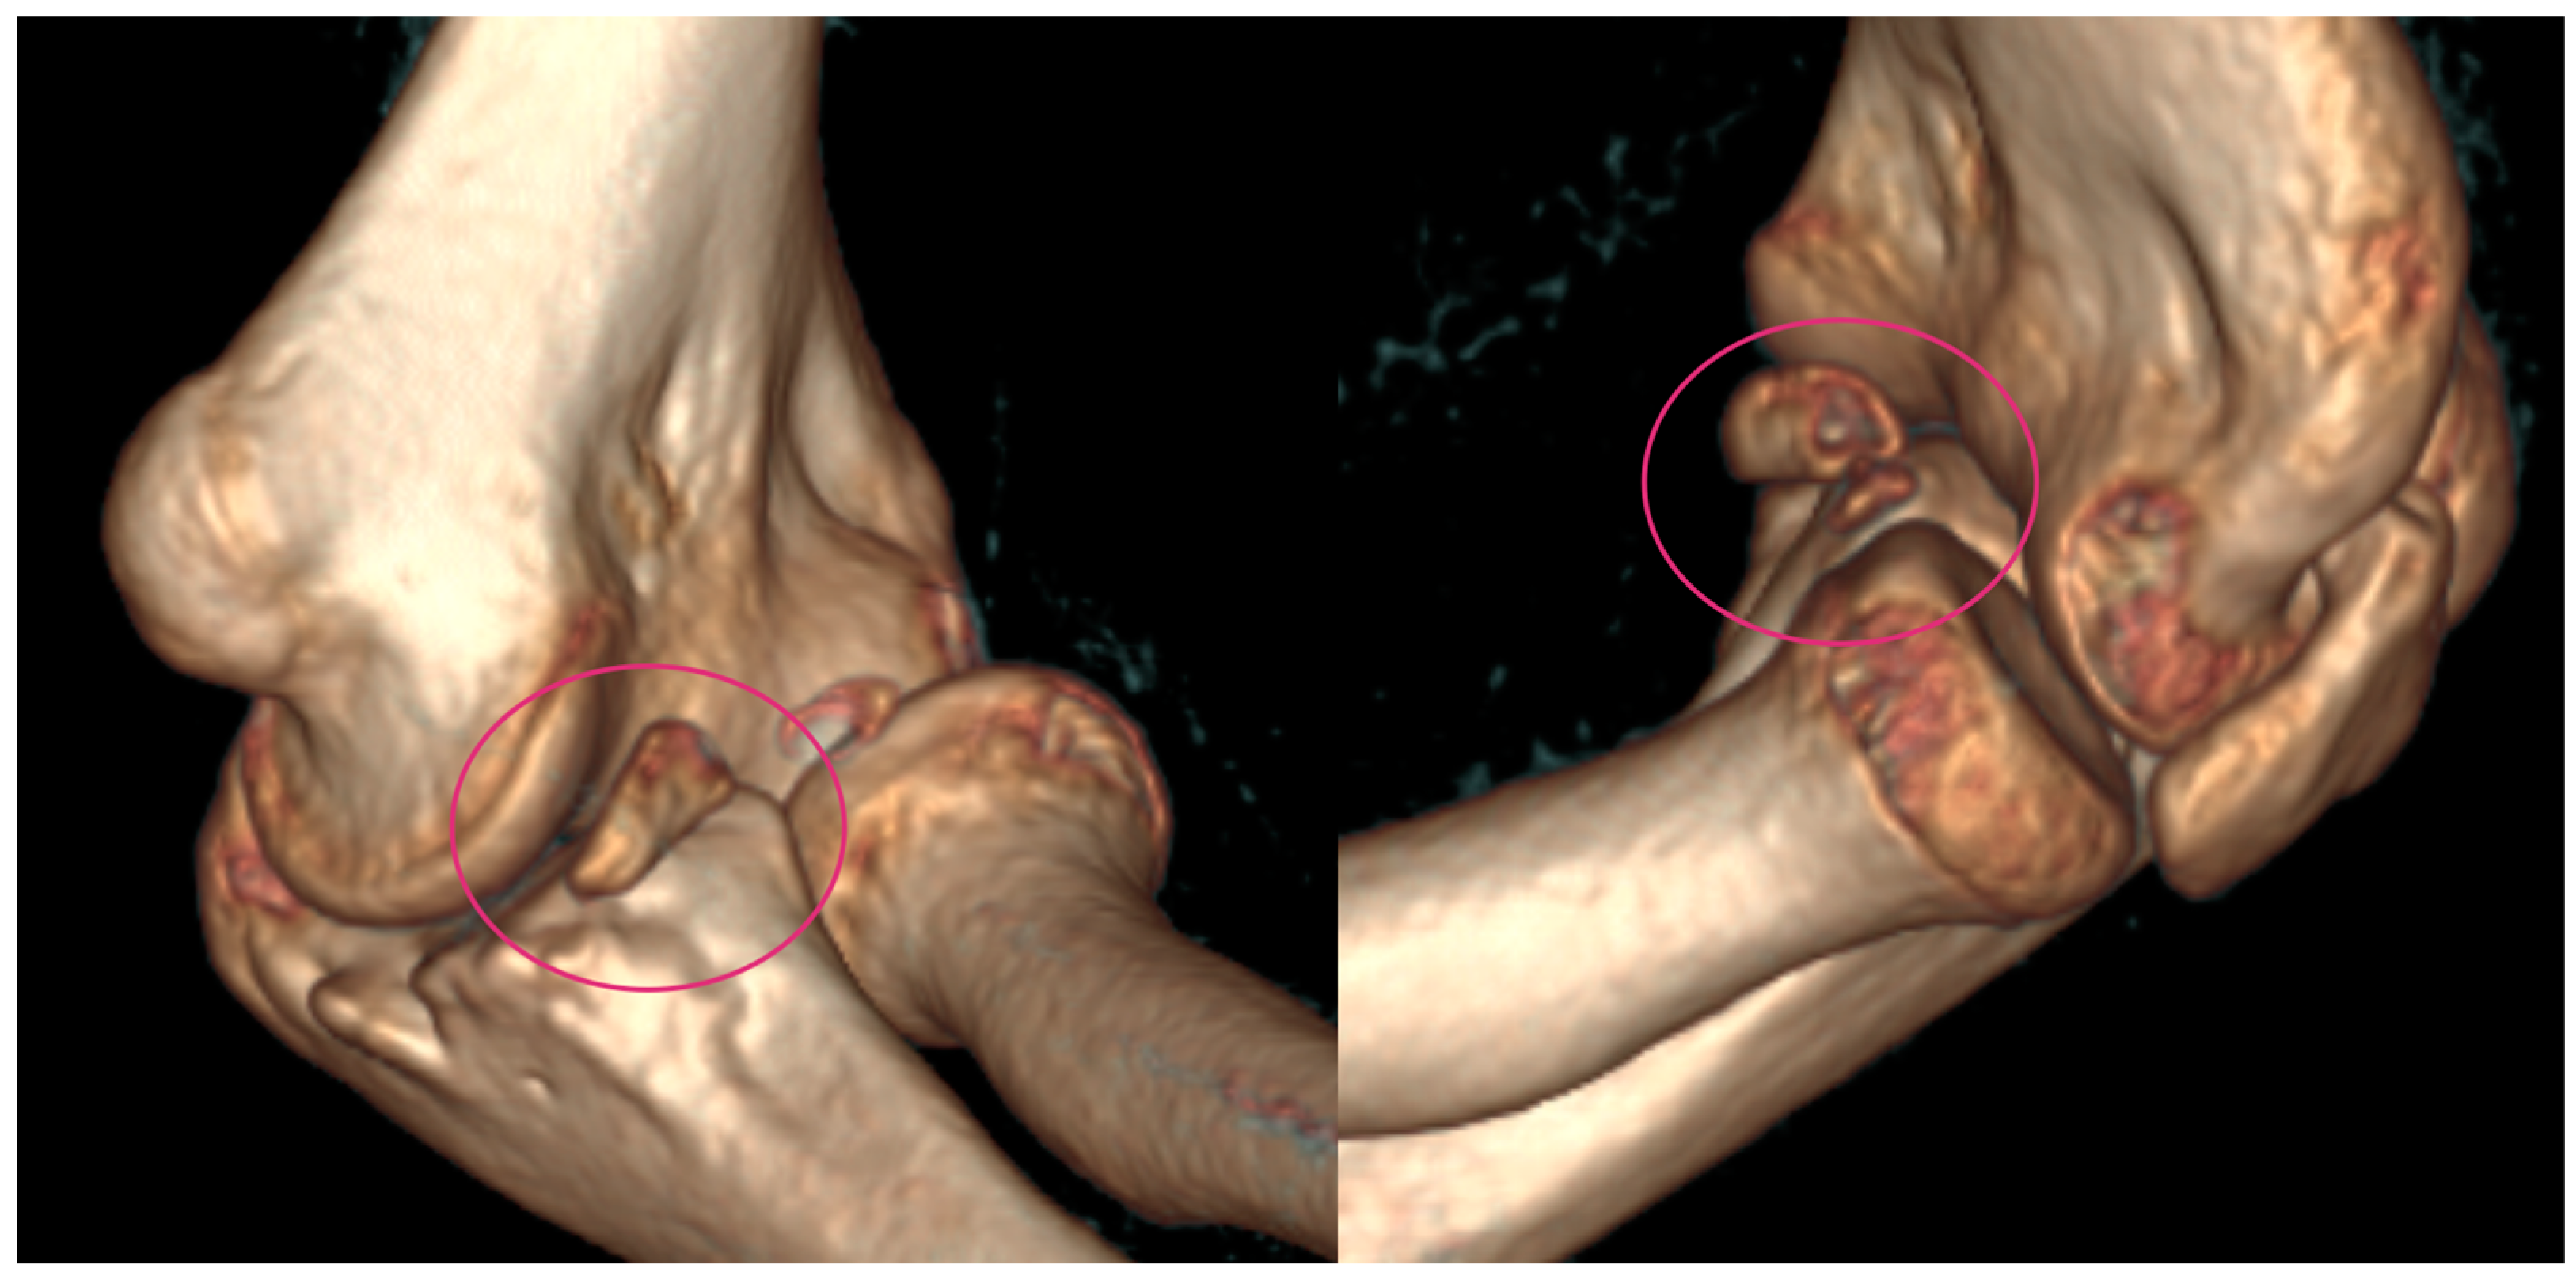

Figure 2.

CT images were provided for surgical planning; the defect can be seen highlighted in the pink circle.